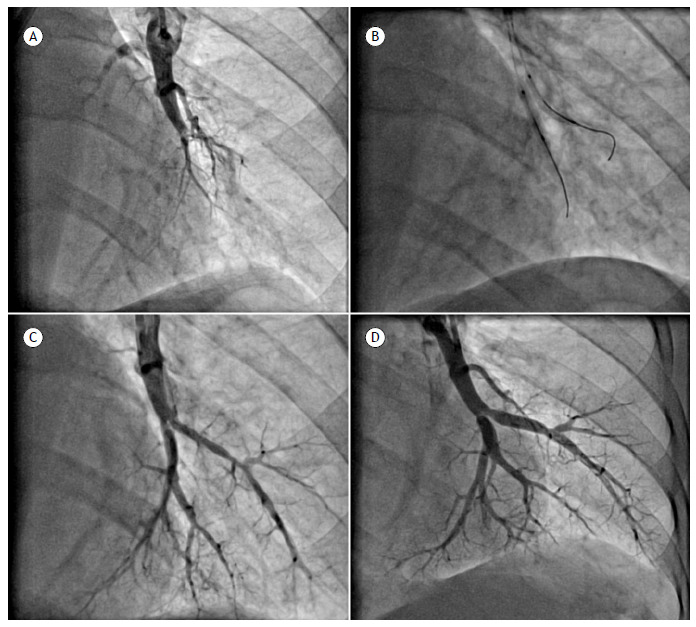

目的:大量慢性血栓栓塞性肺动脉高压(CTEPH)患者不适合肺动脉内膜切除术,可采用球囊肺血管成形术(BPA)治疗。尽管BPA项目最近在巴西开展,但尚未公布任何结果。本研究的目的是评估本中心第一批接受双酚a治疗的患者的临床和血流动力学进展。方法:这是一项观察性研究,纳入了2015年至2020年间巴西一家专业中心BPA项目的23例CTEPH患者。结果:在平均5.6±1.3个疗程和11±2.8个治疗节段/患者后(bpa后平均6.7±2.9个月),平均肺动脉压下降26%(51±11比38±11 mmHg;p < 0.0001),肺血管阻力降低43%(10±3.7 vs 5.7±3.3 WU;p < 0.0001),心脏指数增加22.5%(2.38±0.6 vs. 2.95±0.6 L/min/m2;P < 0.0001)。6分钟的步行距离增加了,功能课程也有所改善。有7%的双酚a疗程后出现急性肺损伤,并有临床表现。没有患者需要插管。在平均38±22个月的门诊随访期间,2例患者因临床恶化和新住院而被转介进行额外的BPA治疗。记录了2例死亡(分别因CTEPH进展和胃肠道出血)。结论:在巴西接受BPA治疗的第一组患者中,有显著的短期和长期临床改善,并发症发生率低。

Results: After a mean of 5.6 ± 1.3 sessions and 11 ± 2.8 treated segments/patient (at a mean of 6.7 ± 2.9 months post-BPA), there was a 26% decrease in mean pulmonary artery pressure (51 ± 11 vs. 38 ± 11 mmHg; p < 0.0001), a 43% decrease in pulmonary vascular resistance (10 ± 3.7 vs. 5.7 ± 3.3 WU; p < 0.0001), and a 22.5% increase in the cardiac index (2.38 ± 0.6 vs. 2.95 ± 0.6 L/min/m2; p < 0.0001). There was an increase in the six-minute walk distance and an improvement in functional class. Acute lung injury with clinical manifestations was observed after 7% of the BPA sessions. None of the patients required intubation. During a mean outpatient follow-up period of 38 ± 22 months, two patients were referred for additional BPA sessions due to clinical worsening and new hospitalizations. Two deaths were recorded (due to CTEPH progression and gastrointestinal bleeding, respectively).